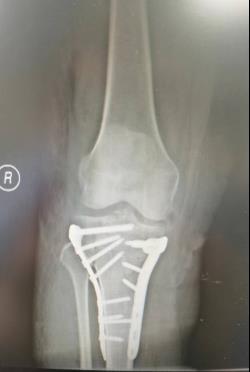

(五)胫骨平台骨折内固定术